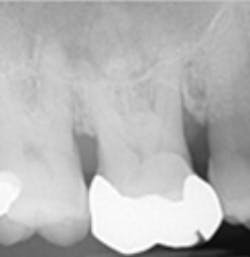

A split- to full-thickness intrasulcular incision was made on the facial of teeth Nos. 2 through 4. Upon completion of flap elevation, an intraosseous cyst associated with the distobuccal root of No. 3 was noted perforating the buccal plate and adherent to the overlying flap (figure 2). A sharp dissection separated the cyst from the flap (figure 3), and the cyst—measuring roughly 1.0 x 0.75 x 0.5 cm—was enucleated intact, leaving an intraosseous defect (figures 4a and 4b).